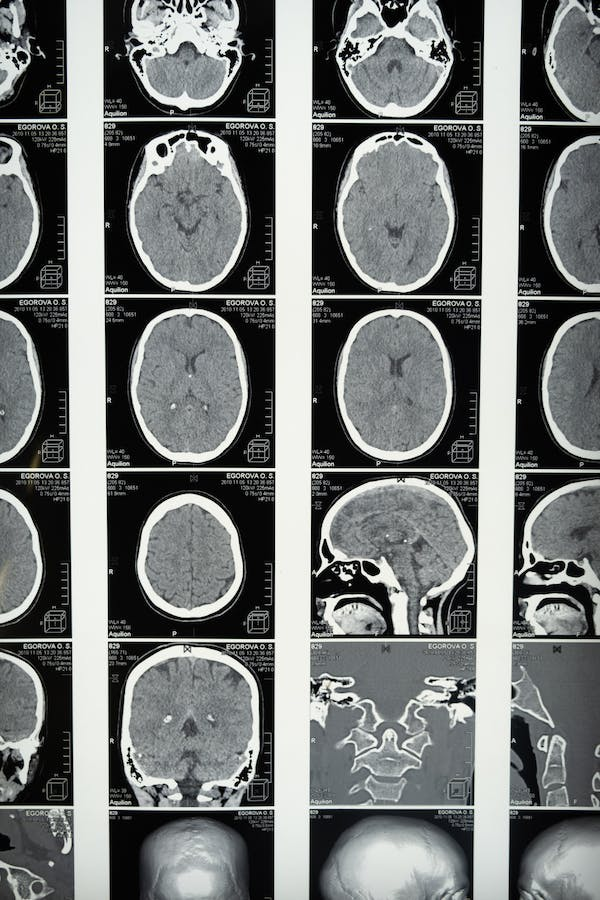

El deterioro cognitivo es una característica fundamental de la esquizofrenia. Entre los factores probables en la persistencia de los déficits cognitivos en este trastorno se encuentran los cambios en el tejido cerebral a lo largo del tiempo.

El papel de la microestructura de la materia blanca cerebral para mantener la velocidad de procesamiento y otras medidas cognitivas ha sido reportado en diversas investigaciones. Así, la velocidad de procesamiento y la memoria de trabajo dependen de operaciones de redes neuronales a gran escala y larga distancia.

Lo anterior es respaldado por fibras axonales neuronales mielinizadas. De esta forma, las limitaciones cognitivas en las personas con esquizofrenia coinciden con déficits en la microestructura de la materia blanca cerebral.

La rehabilitación cognitiva ha mostrado ser efectiva en personas con esquizofrenia. Así, incluso se han observado efectos en la disminución de la pérdida de materia gris en las etapas iniciales de la afección. Sin embargo, esto dependerá de la reserva cognitiva previa del sujeto y sus problemáticas particulares, siendo este un abordaje personalizado.